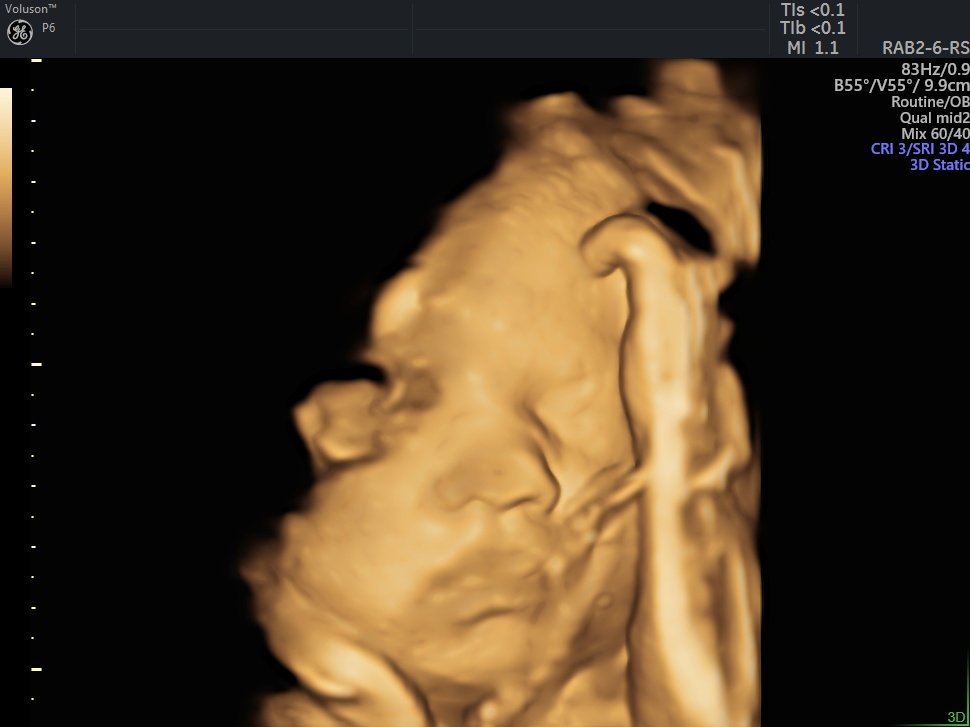

4 Boyutlu (Renkli) Ultrason ve Doppler Ultrasonografi

4 D Ultrasonografi